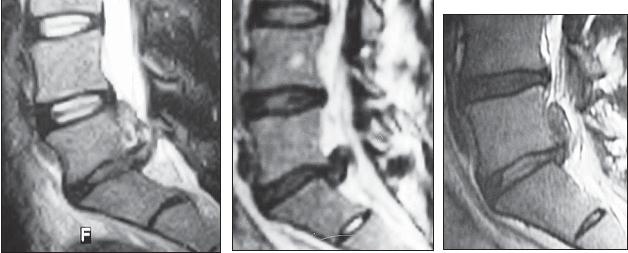

На серии снимков МРТ № 25 наблюдаются дорсальные грыжи межпозвонковых дисков в поясничном отделе позвоночника в сегментах LIV-LV Lv—SI Такие комбинации, в которых образуются по нескольку грыж, межпозвонковых дисков одновременно, случаются довольно часто на более поздних стадиях развития дегенеративно-дистрофического процесса. В общем, беда не приходит одна, «несчастье» любит, компанию МРТ № 26